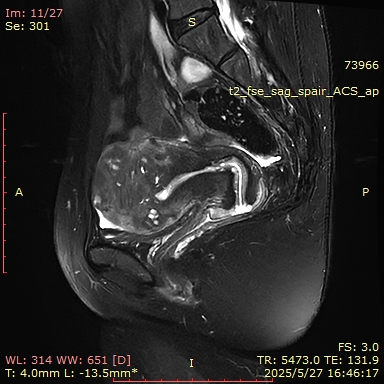

MRI(2025-05-27):子宫肌层增厚,其内信号欠均匀,肌层内见一等类圆形T2WI低信号,其内可见T1WI高信号,大小约为40mm*39mm。左侧附件区可见类圆形短T2异常信号影,大小约为8mm*5mm;右侧附件形态、大小、信号未见明显异常。盆腔少量积液。